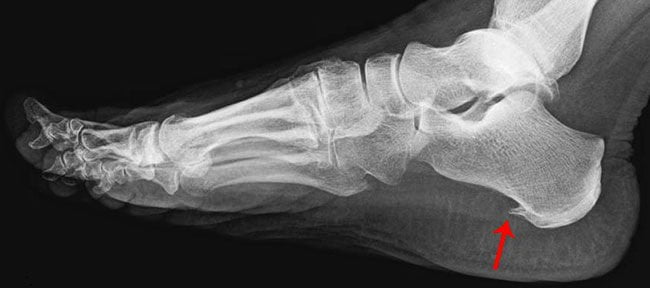

Шипы пяточных костей

Остеофиты на пятке (по МБК 10 болезнь имеет номер M25) развиваются вследствие нарушения кальциевого обмена либо по причине воспалительных процессов в стопе. Пяточные наросты диагностируются у 50 % людей с тяжелыми заболеваниями позвоночника или суставов.

Симптомы и лечение остеофитов на пятке определяются степенью запущенности патологии и ее первопричиной. Терапия для таких пациентов — только комплексная.

Если остеофиты не мешают человеку ходить, не вызывают сильной боли, для облегчения состояния можно лечиться народными средствами.

При крупных остеофитах, поражающих пяточную кость и мягкие ткани, показано хирургическое лечение (можно практиковать в Израиле и других странах). Однако хирургическое лечение очень болезненное и не всегда может полностью избавить от патологии.